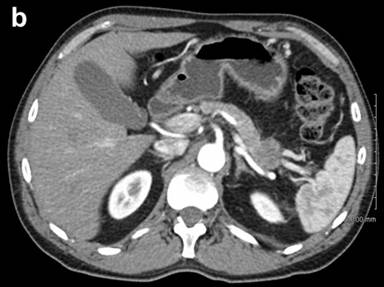

A previously healthy, non-diabetic 56-year-old man presented in March 2010 with abdominal pain and nausea to an outside facility. Following an extensive workup, including imaging, he was diagnosed with chronic pancreatitis. Repeat CT, one year later on re-presentation with jaundice, demonstrated an atrophic pancreas and a 3 cm hypodense area in the tail of the pancreas with splenic vein invasion as well as a second mass of 2 cm in the head of the pancreas with invasion of the portosplenic confluence (Figure 1). Endoscopic ultrasound with fine-needle aspiration confirmed the presence of both masses with the pancreas head lesion being concerning for invasion into the splenoportal vein confluence (Figure 2). Biopsy of the head mass demonstrated undifferentiated carcinoma with osteoclast-like giant cells. Based on these findings, diffuse involvement of the entire gland with neoplastic process was suspected.

Figure 2. Pancreatic head mass abutting portal vein. |